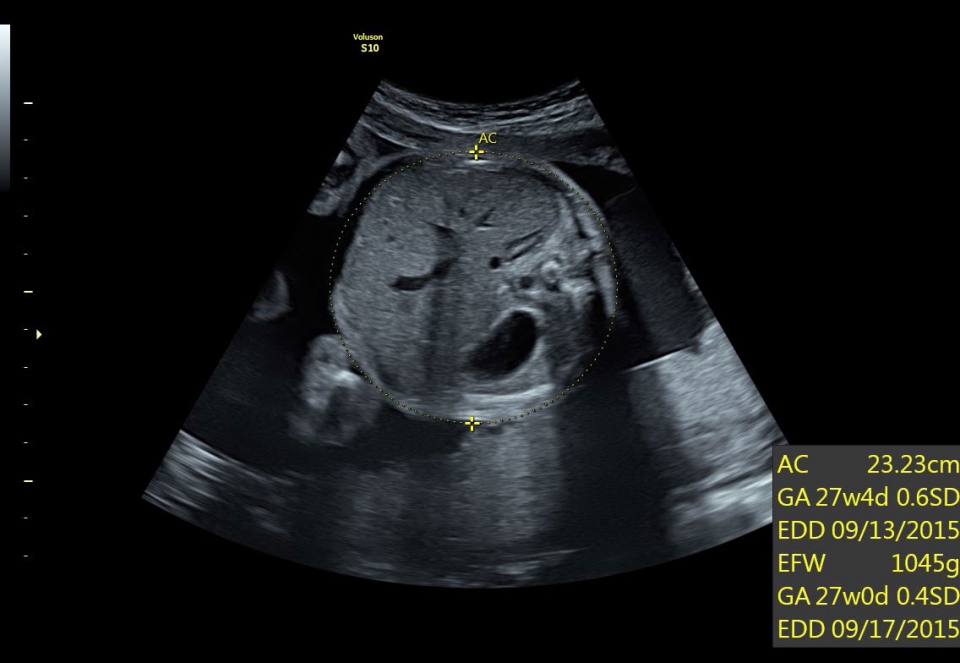

УЗИ аппарат Voluson S10 позволяет проводить обследования высочайшего уровня с максимальной точностью диагностики. Благодаря технологии Voluson Core Architecture достигнут высокий уровень качества изображений с возможностью последующей обработки и анализа даже после проведения скрининга. Технология HDlive делает изображения удивительно реалистичными и объемными.

• SonoBiometry (Полуавтоматическая биометрия): Эта технология позволяет проводить измерения биометрических параметров плода, таких как бипариетальный размер, окружность головы, окружность живота, длина бедра и длина плеча. Она упрощает процесс получения точных и надежных измерений.

• SonoNT (Оценка воротникового пространства) и SonoIT (Оценка внутричерепного пространства): Эти технологии позволяют проводить полуавтоматическую оценку толщины воротникового пространства и размеров IV желудочка головного мозга плода в I триместре беременности. Они обеспечивают более точную оценку этих параметров с минимальными усилиями.